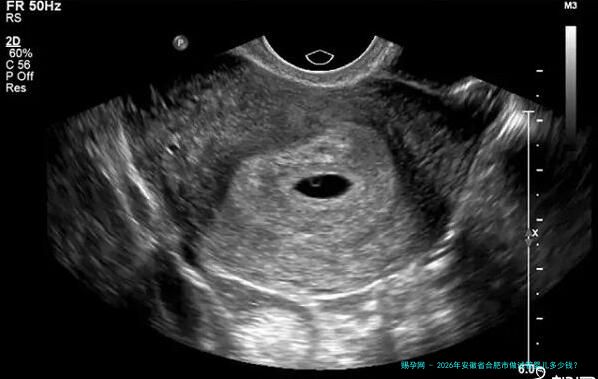

促卵泡发育药物及卵泡监测费用:医生会根据女性的卵巢机能和体质状况制定个体化的促排卵方案。促排卵药物分为国产和进入口,价格差异较大。同一时间,在促排卵期间需要屡次进行B超监测卵泡发育情况和抽血检查激素水平。这部分费用一般来说在20000元至40000元。